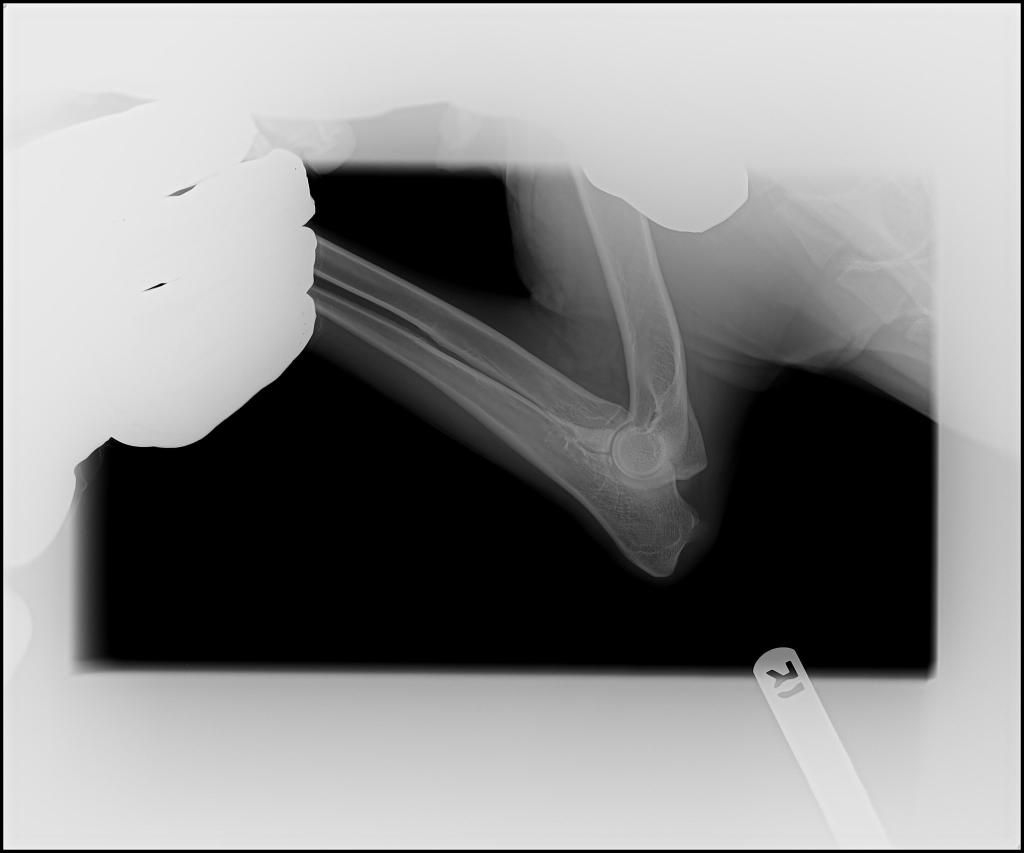

- Hips: OFA Good

- Elbows: OFA Normal

Rocky’s Hip and Elbow X-rays: